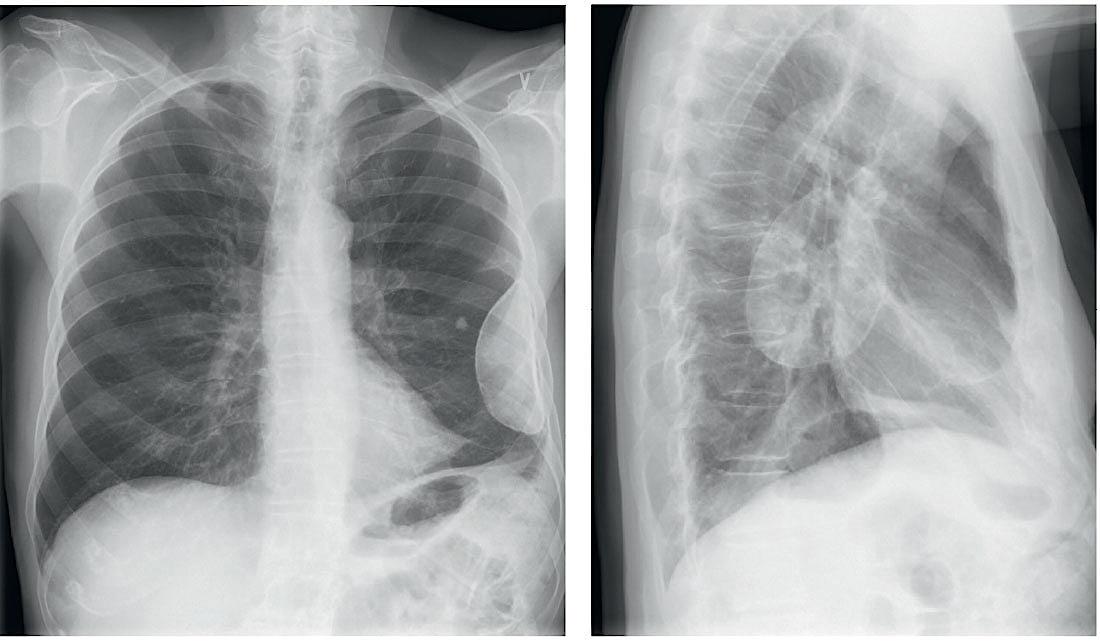

En røntgenoptagelse af thorax i to planer med patienten stående viser en 10 × 4 × 7,5 cm stor halvkugleformet, velafgrænset, pellucid forandring i venstre thoraxvæg lateralt. Forandringen var et tilfældigt fund hos en 83-årig mand, der var henvist pga. langvarig hoste, og behandlingen er en historisk kirurgisk metode, oleothorax.

Hos denne patient blev der foretaget en succesfuld behandling, da der ses en 6 mm stor parenkymforkalkning lige medialt for »plomben«, hvilket er foreneligt med helet tuberkulosefokus.